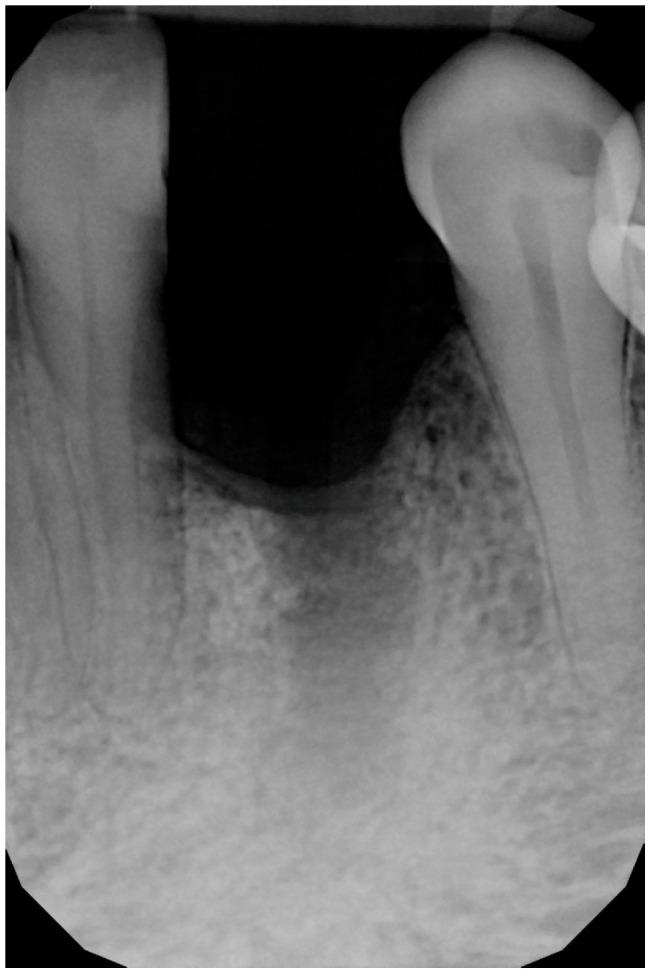

Guided bone regeneration (GBR) has represented a challenge for clinicians in the past 30 years, and the literature has well described many different surgical options such as d-PTFE membranes, titanium grids, or autogenous bone harvested from the posterior mandible. All of the previously mentioned techniques have shown a high rate of complications but, in the last decade, a new membrane made of xenogenic bone was introduced. Most of the publications regarding its application report very few and mild complications. In this article we will suggest a new application using segmented xenogenic bone sheets instead of autogenous bone to correct severe ridge deformity. : Xenogenic bone sheets have been studied extensively over the past decade and have proven effective, with a very low rate of complications when used to reconstruct bone atrophies. The technique presented in this paper aims to reduce morbidity, avoid the need for intra-oral graft harvesting, and minimize both surgical time and post-operative discomfort. : Xenogenic bone sheets of equine origin were used to reconstruct severe 3D bone defects in five patients requiring dental implants. The segmentation of the sheet allowed the operator to rebuild the missing bone walls and achieve optimal anatomy without compromise. Furthermore, using different sizes and thicknesses of the bone sheets allowed safe procedures preventing early exposure of the membranes. CBCT of the defects before and after 8 months of healing were measured with Exocad software to assess the volumetric gain. Histological analysis performed on one site showed integration of the bone lamina and live bone underneath. : In all five cases evaluated the ridge deformities were successfully corrected and all patients' implants have functioned for more than two years to date. The average horizontal bone gain in these five cases was 6.18 mm (±1.19 mm) while the vertical gain was 9.70 mm (±2.39 mm). : This new application of flex cortical sheets simplifies the surgical procedure for both operator and patient, reduces morbidity and post-operative complications, and shows promising signs for resolving complex 3D bone reconstructions.

在过去30年里,引导骨再生(GBR)一直是临床医生面临的一项挑战,文献中已经详细描述了许多不同的手术选择,如双层聚四氟乙烯(d-PTFE)膜、钛网或从下颌后部获取的自体骨。上述所有技术都显示出较高的并发症发生率,但在过去十年中,一种由异种骨制成的新型膜被引入。关于其应用的大多数出版物报告的并发症很少且很轻微。在本文中,我们将提出一种使用分段异种骨片代替自体骨来矫正严重牙槽嵴畸形的新应用。:在过去十年中,异种骨片已被广泛研究,并已被证明是有效的,用于重建骨萎缩时并发症发生率非常低。本文介绍的技术旨在降低发病率,避免口内取骨的需要,并将手术时间和术后不适降至最低。:使用马源异种骨片为五名需要种植牙的患者重建严重的三维骨缺损。骨片的分段使手术者能够重建缺失的骨壁并实现最佳解剖结构而不受影响。此外,使用不同尺寸和厚度的骨片可进行安全操作,防止膜过早暴露。使用Exocad软件测量愈合8个月前后缺损的锥形束计算机断层扫描(CBCT),以评估体积增加情况。对一个部位进行的组织学分析显示骨板与下方活骨的整合。:在评估的所有五例病例中,牙槽嵴畸形均得到成功矫正,所有患者的种植体至今已正常使用两年多。这五例病例的平均水平骨增量为6.18毫米(±1.19毫米),而垂直增量为9.70毫米(±2.39毫米)。:这种柔性皮质骨片的新应用简化了手术者和患者的手术过程,降低了发病率和术后并发症,并显示出解决复杂三维骨重建问题的良好前景。